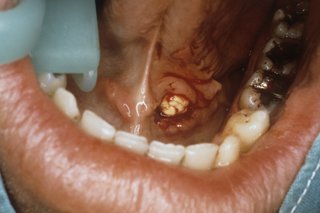

عارضه ای به نام سنگ بزاقی!!!

احتمالاً نام سنگ های بزاقی تا به حال به گوشتان نخورده است! همانطور که به گوش من نخورده بود! آنها دانه های سنگ مانندی هستند با نام علمی سیالولیت، که سر و کله شان در بزاق دهان پیدا شده و می توانند با مسدود کردن جریان بزاق، منجر به درد و ناراحتی شوند.

آنها در بعضی مواقع خود را نشان می دهند و گاهی پنهان می شوند. اندازه و سایز متنوعی دارند اما معمولاً سخت هستند و سفید رنگ.

* وجود زخم یا توده دردناک زیر زبان